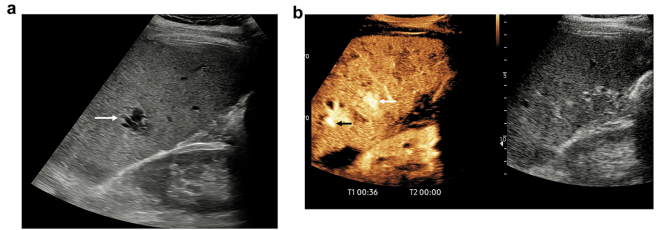

复杂肾囊肿:Bosniak分类的超声进化

CEUS检出>2mm分隔的灵敏度超CT,78岁患者18mm肾囊肿经CEUS升级为Bosniak IIF类